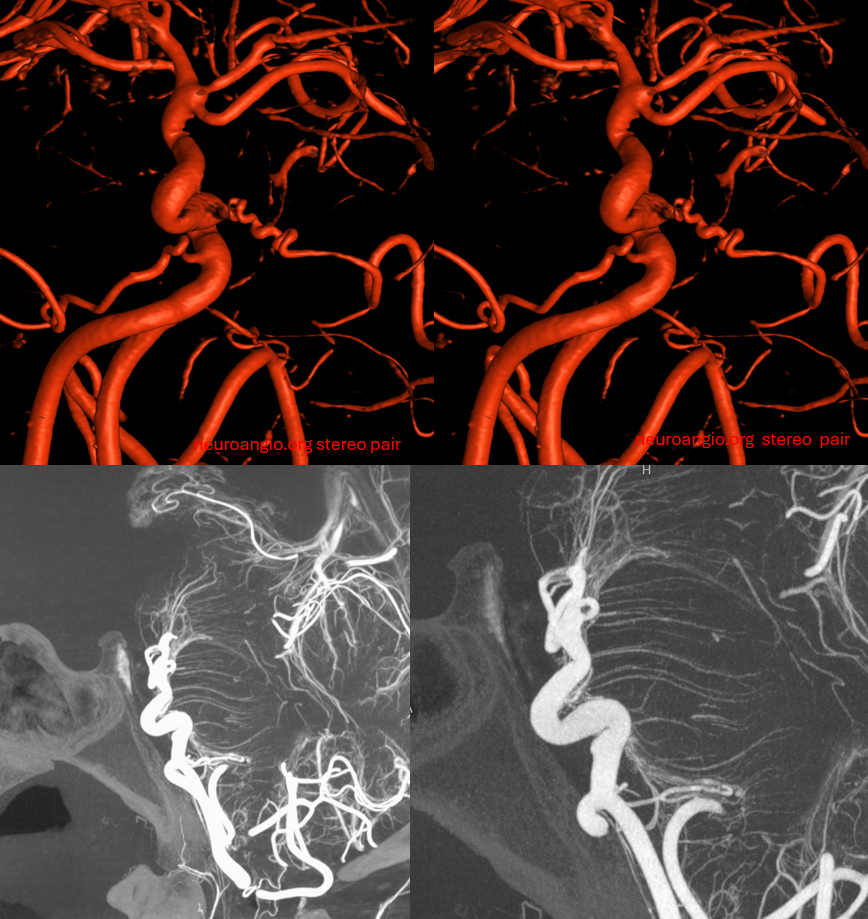

Stereos

Red/cyan anaglyph stereo

Native stereos, retro style

Usually the finding is bilateral, as it is here (see unilateral Case 4 below)